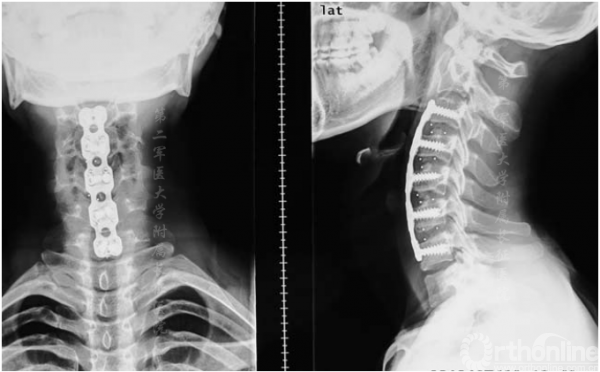

手术后6个月内,JOA评分从术前平均14分提高到术后平均16.3分。所有患者的JOA恢复率均较为满意。内在肌肉、腕部屈肌和伸肌以及二头肌和三头肌的肌力平均提高了1级。骨移植完全融合(图4),颈椎管容积和颈矢状位满意(图5)。没有发生与手术有关的并发症。

图4.术后6个月x线片显示内固定位置满意,椎体对位齐和骨融合